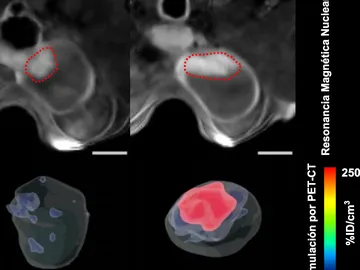

Los tumores de vejiga se reducen en un 90% con el uso de nanorrobots